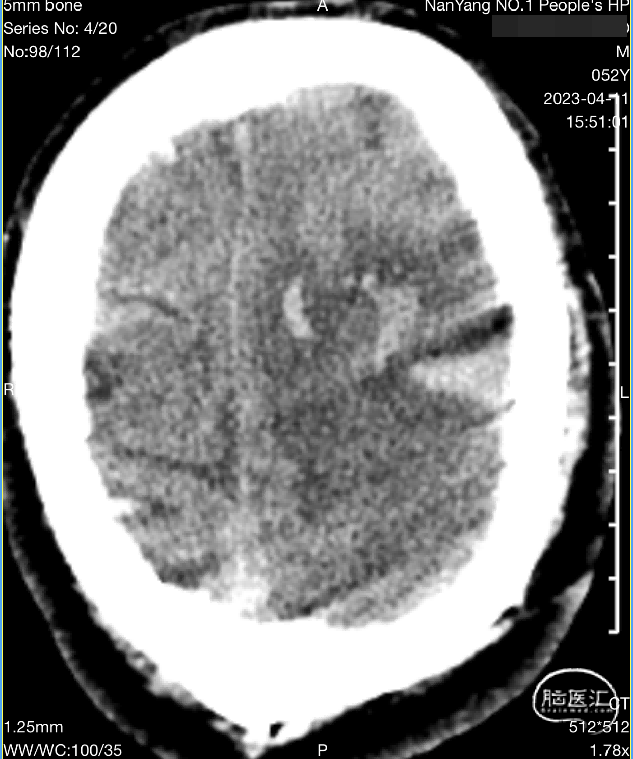

入院影像检查

MRV可见上矢状窦及右侧横窦充盈缺损。